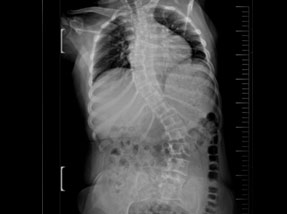

• Post Surgery

• Pre-Surgery

Case 1